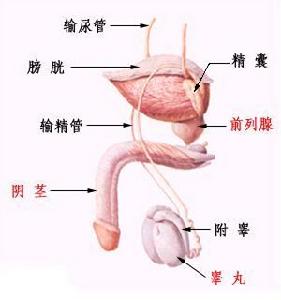

睾丸破裂主要是由于外伤一起的,具体还可表现为睾丸疼痛、睾丸肿胀、睾丸脱位等,对男性来说要遭受很大的痛苦,治疗不及时的话甚至影响到性功能和生育能力。那么睾丸破裂怎么办?具体症状是什么?

1、睾丸破裂时睾丸肿胀,硬,剧痛与触痛。

2、睾丸破裂会有睾丸脱位的症状,睾丸被挤压到阴囊以外的部位。如腹股沟管,股管、会阴等部位的皮下,局部剧痛、触痛、痛侧阴囊空虚。

3、睾丸破裂时阴囊皮肤瘀斑,血肿,开放性损伤阴囊撕裂,睾丸外露。

4、睾丸破裂时会有剧疼甚至昏厥,阴囊血肿,触痛明显,睾丸轮廓不清。